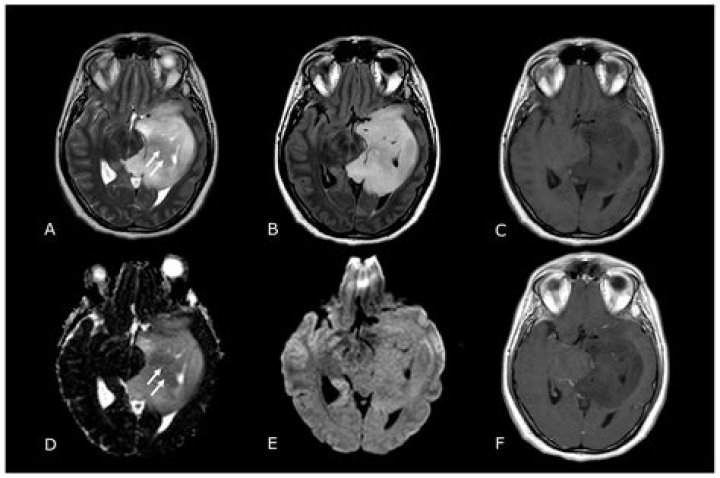

Read JournalCranial computed tomography (CT) and magnetic resonance imaging (MRI) with and without contrast media are widely used for primary diagnosis of brain tumor...